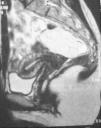

Es repetida la ecografía abdominal donde se visualiza un útero y anejos sin alteraciones significativas pero hallándose en región pararrectal lesión sólida de 15×27×19mm. Dados los hallazgos se le practica ecografía endorrectal que no consigue ver ni filiar la lesión por lo que se decide realización de nueva RNM en nuestro centro, siendo informada como lesión presacra de bordes bien definidos, que sugieren la presencia de quiste o lipoma presacro dada la localización y relación con estructuras anatómicas adyacentes, sin objetivarse infiltración de tejidos circundantes al mismo (fig. 1).

Con estos hallazgos se decide intervención quirúrgica realizándose abordaje posterior de Kraske sin encontrarse lesión alguna en espacio presacro pero con sensación de masa intraabdominal durante la disección de dicho espacio. Se decide nueva laparotomía exploradora donde se evidencia la presencia de gran lipoma del meso-apéndice cecal, dentro de un profundo y laxo fondo de saco retrorrectal (fig. 2). Se procede a exéresis de la pieza siendo informada como proliferación lipomatosa de mesoapéndice de ciego.